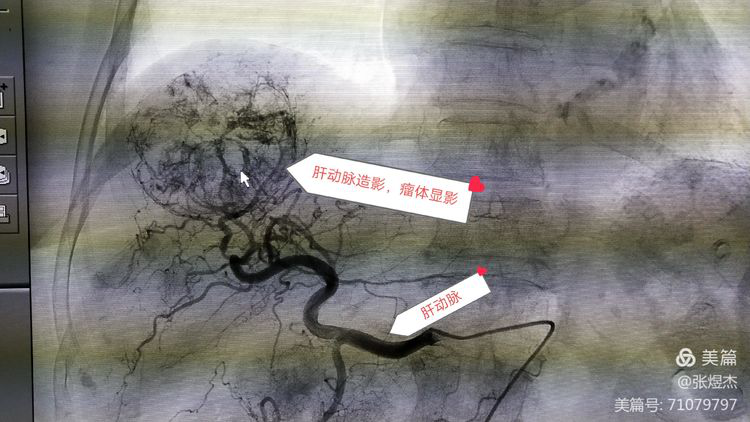

肝癌灌注化疗加栓塞术(TACE),是通过数字血管造影机(DSA)逐级行肝动脉造影,找到肝脏内的肿瘤及供血动脉。

这就是我们在实际手术中,通过肝动脉造影确定肝脏肿瘤的具体位置以及它的供血动脉。